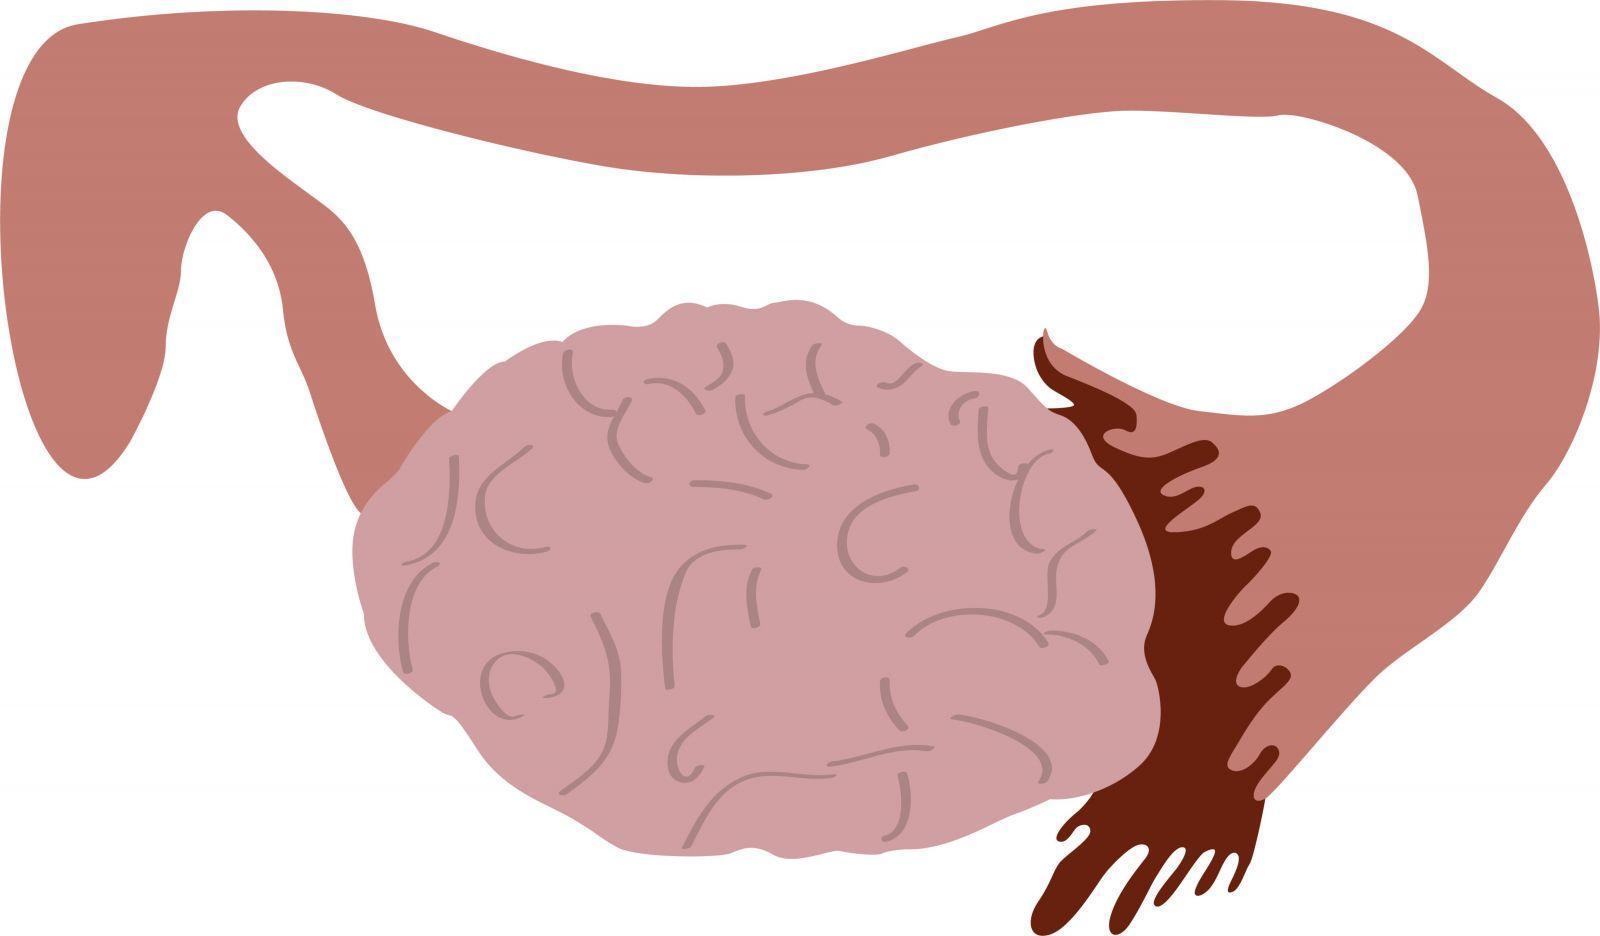

Bu hormonal dengesizlik polikistik over sendromuna pco yumurtalıklarda birçok küçük iyi huylu kist oluşmasına neden olur. Polikistik over sendromlu hastaların kanında normalden fazla insülin bulunuyor ancak vücut hücreleri insüline yeterli yanıt vermiyor. Kadın hastalığıdır ve bu durumda kadınlar normalden daha fazla erkek hormonu üretir. Ayrıca çoğu zaman yaşam kalitenizi etkileyen diğer semptomlara yol açar.

Yumurtlama bozukluğu oluşumuna neden olarak kısırlığa zemin hazırlar. Hormonal bozuklukların yol açtığı p olikistik over sendromu yumurtalıkların androjenleri fazla salgılamasıyla ortaya çıkar. İyi huylu olmalarına rağmen bu kistler dokularda iltihaplanmalara neden olur. üreme çağındaki kadınlarda sık görülür adet düzensizliğine neden olur hamilelik şansını azaltır.